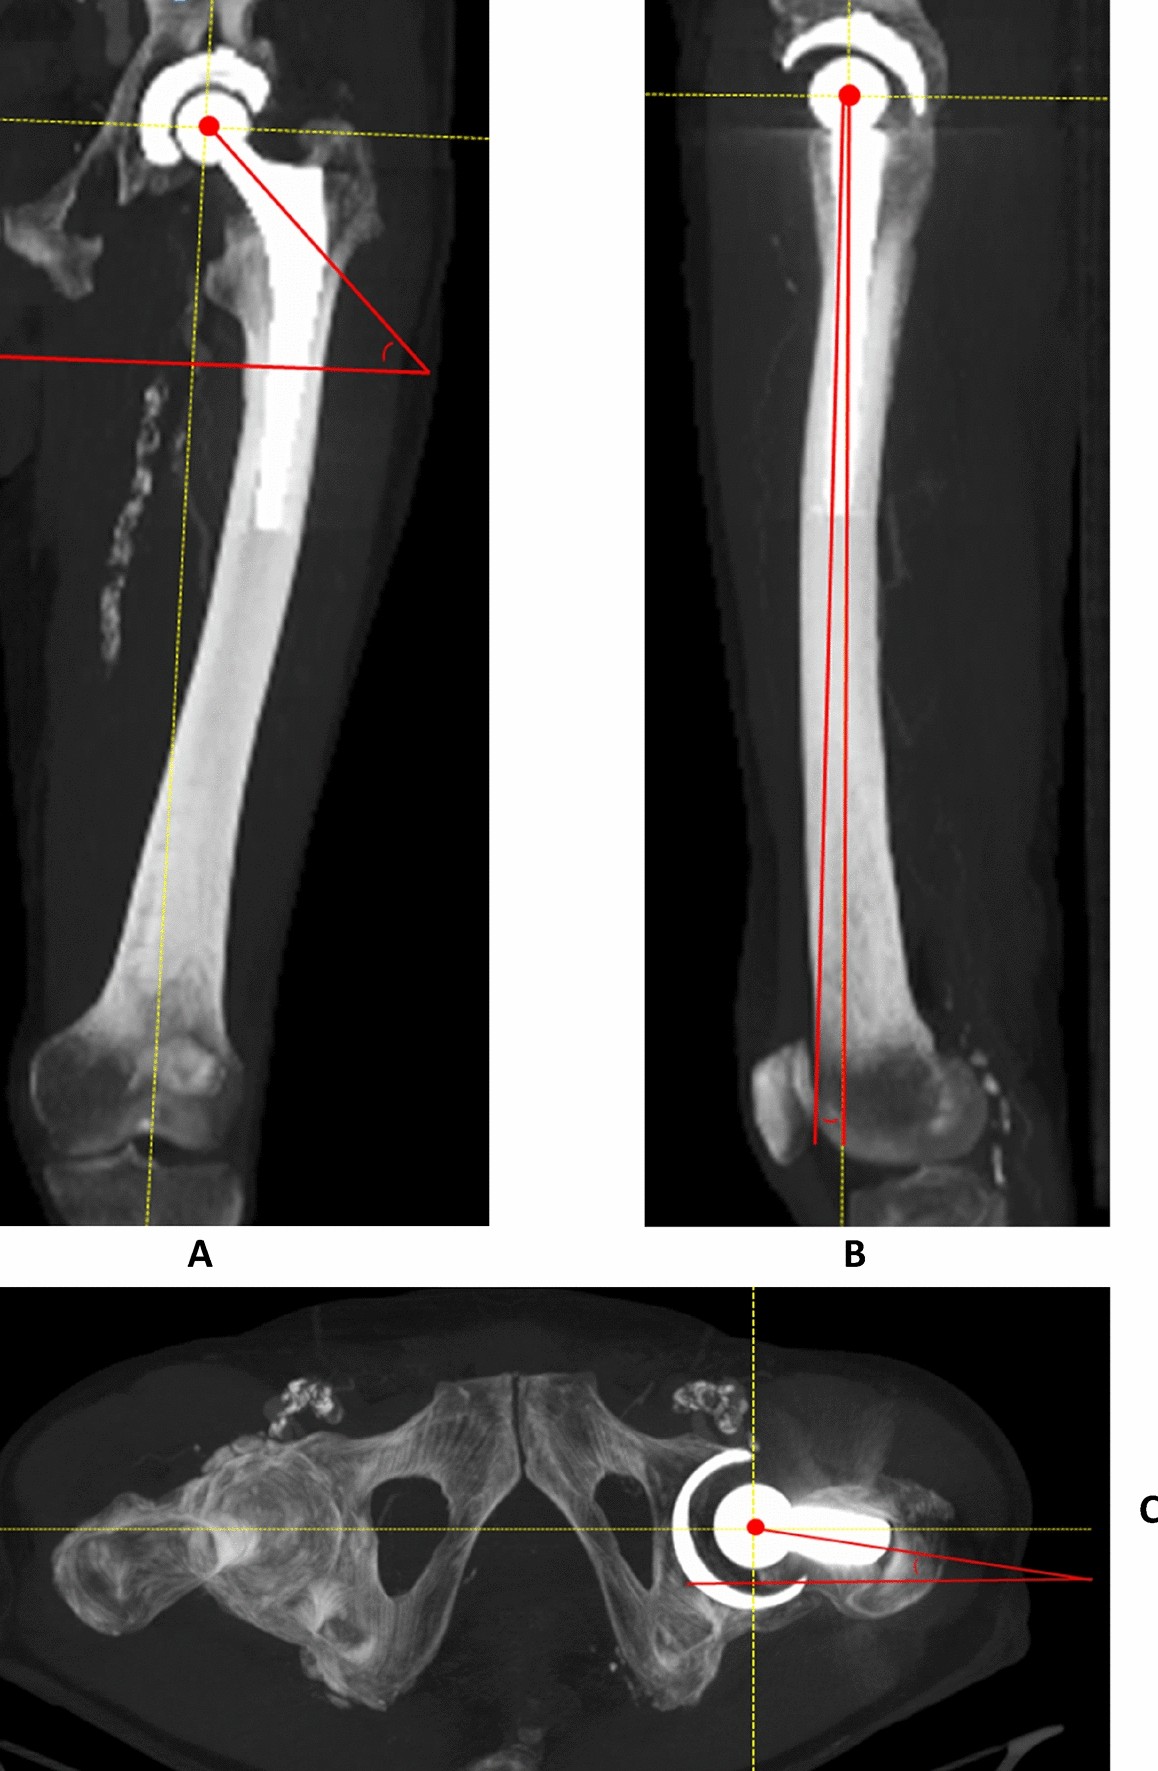

Figure 2

Measurement method of coronal inclination (CIF’, defined as the angle between the line through the longitudinal axis of the neck of the femoral component and the horizontal on the mechanical femoral axis) (a), sagittal inclination (SIF’ defined as the angle between the line from the center of the femoral head to through the middle of the femoral neck, in relation to the mechanical femoral axis) (b) and transverse version (TVF’, defined as the angle from the center of the femoral head through the femoral neck, in relation to the horizontal on the mechanical femoral axis, with the posterior condylar plane as distal reference) (c) of the femoral component on 3-D MIP constructed CT (mechanical femoral axis/horizontal displayed as dashed line).